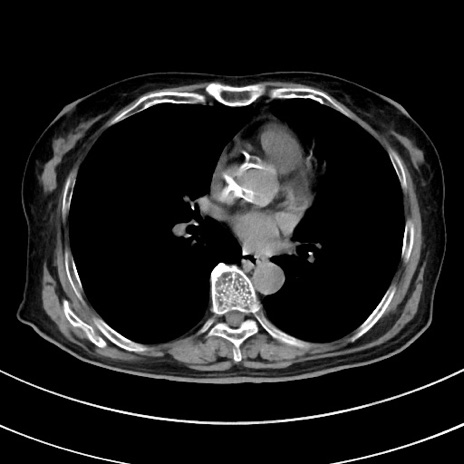

症例33(横断像)

【症例】70歳代 女性

【主訴】心窩部痛

【現病歴】延髄病変の精査・加療にて神経内科入院中。本日より心窩部痛あり。

【身体所見】右下腹部を中心に圧痛と反跳痛あり。

【データ】WBC 10900、CRP 0.02